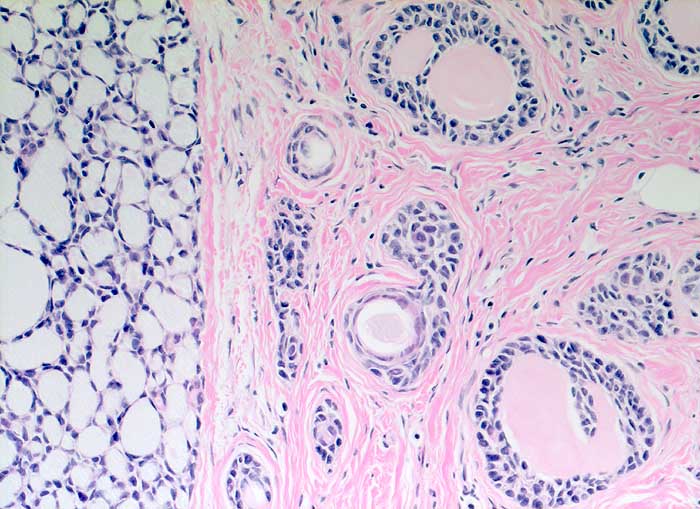

Adenoidzystisches Karzinom

Kribriforme Tumormasse. Die Hohlräume sind gefüllt mit mucoidem Material oder eosinophilem amorphem Material.

Adenoidzystische Karzinome kommen vor allem im Bereich der Speicheldrüsen vor, treten aber auch in anderen Organen auf. Sie machen weniger als 0.1% - 0.2% der Mammakarzinome aus.

Histologie

200